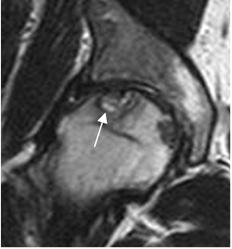

Fig 23. Osteonecrosis de cadera.

RM coronal en T2. Signo de la doble línea hiperintensa en T2, típico de la osteonecrosis.